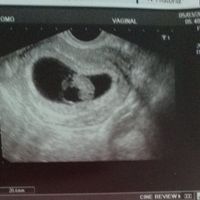

Hola! Quería preguntaros si entendéis el método Ramzi si sabéis que puede ser. Os lo agradecería muchísimo. Es una ecografía de 7 semanas